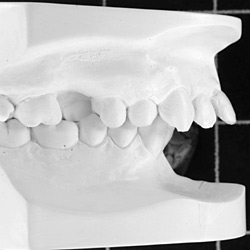

Kieferorthopädisch-kieferchirurgische Kombinationsbehandlungen

Wenn nicht nur die Zähne, sondern auch der Oberkiefer oder der Unterkiefer verändert werden müssen, so kann dies mit Spangen nur während der Wachstumsphasen gemacht werden.

Ist das Wachstum beendet, so kann diese Kieferveränderung nur operativ korrigiert werden.

Der Kieferorthopäde verschiebt die Zähne, der Kieferchirurg operiert den Kiefer. Anschließend sorgt der Kieferorthopäde wieder dafür, dass alles zusammenpasst.